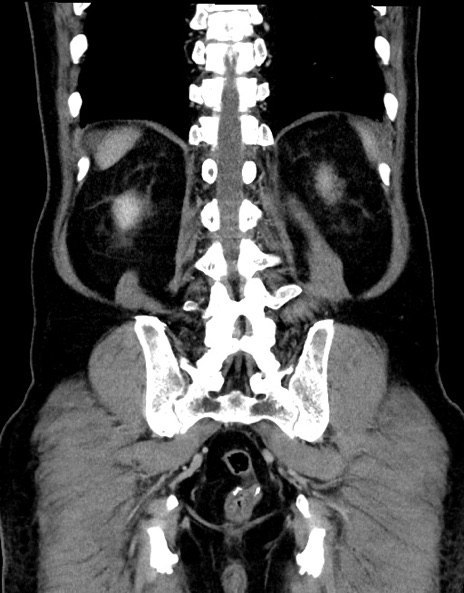

症例15(冠状断像)

【症例】70歳代男性

【主訴】腹痛

【現病歴】今朝から腹痛あり。全体的に痛い。特に左上の方。排ガスが今日はない。冷や汗が出る。

【既往歴】直腸癌術後

【身体所見】左側腹部〜上腹部に圧痛あり。腹膜刺激症状明らかなではない。軽度反跳痛。左下腹部に術後瘢痕あり。

【データ】WBC 7700、CRP 0.02